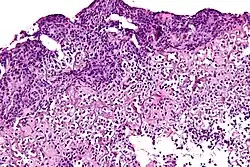

![]() | Lepromatous leprosy | Skin biopsy showing epidermal atrophy and multiple dermal infiltrates. | Category: Histopathology of leprosy | Leprosy |